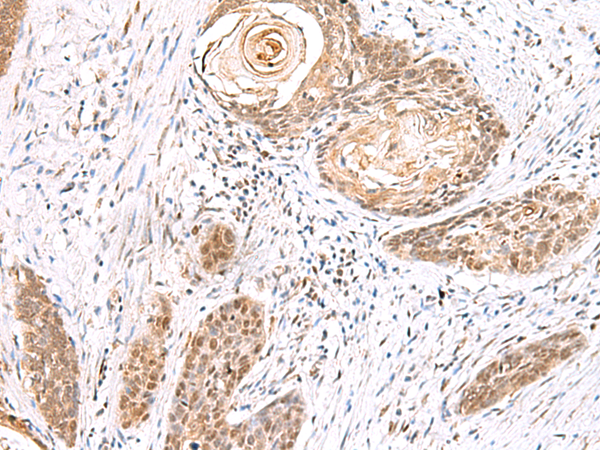

分类: 科研抗体货号: P10134别名: RZF应用: IHC反应种属: Human, Mouse, Rat